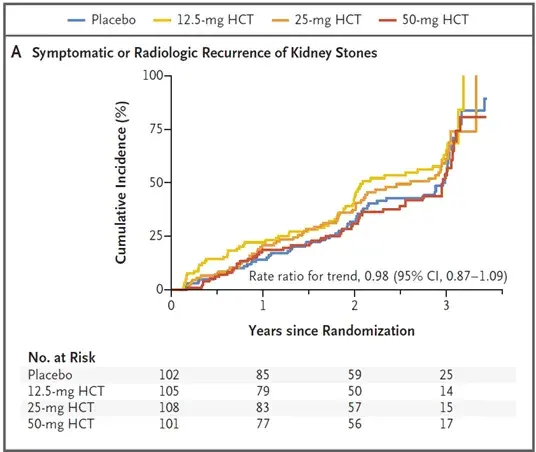

O tratamento da Nefropatia por IgA está longe de ser simples, confere o Trial mais recente que avaliou eficácia do Micofenolato.